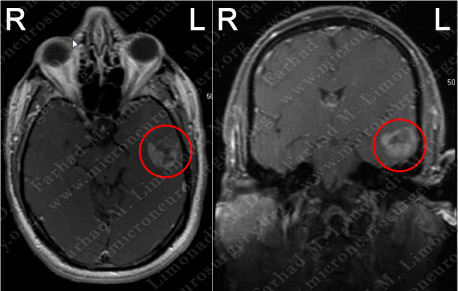

Imaging

MRI scan of the patient's brain showed a large left temporal brain tumor.